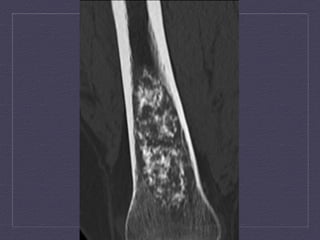

Axial  and  coronal  CT  demonstrates  septated,  ly:c  lesion  in  the   intertrochanteric  region  with  significant  thinning  of  the  posterior  cortex